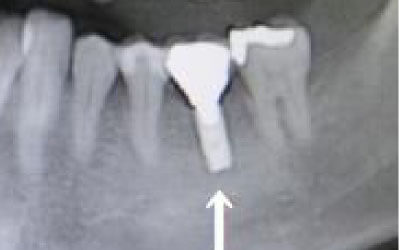

2 神経を傷つけるリスク

インプラントの手術では、顎の骨を通る神経を傷つけるリスクがあります。

しかし、事前にCTでしっかりと撮影し、三次元的に神経との距離を計測して治療計画を立てることで、心配は不要です。

また、当院では削りすぎを防ぐためのストッパーも使用しています。